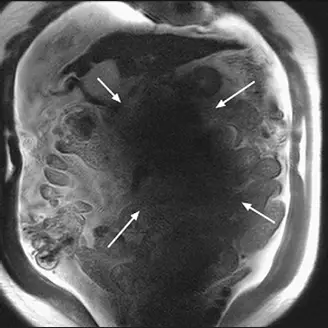

本題提供一張腹部冠狀面(Coronal)的 T2 權重 MRI 影像。

- 視覺特徵:影像中央出現大範圍的異常訊號缺失(黑影,白色箭號所指處),而靠近體表周邊的組織訊號相對極度明亮。同時可以觀察到腸道周圍有游離水分(腹水)。

- 臨床意義:這種「中央暗、周圍亮」的典型表現為介電效應偽影(Dielectric effect artifact),又稱為 B1 磁場不均勻偽影。此偽影在 3T 腹部 MRI 極為常見,尤其當患者體型較大或有大量腹腔積液(高導電性與介電常數)時會更加明顯。因為射頻(RF)波長在人體內縮短,產生破壞性干涉,導致腹部深處的激發翻轉角(Flip angle)不足,進而造成嚴重的訊號缺失。

圖中箭號所指的黑影為介電效應偽影(Dielectric artifact)。在 3T 高階 MRI 掃描中,射頻脈衝(RF pulse)的頻率較高(約 128 MHz),其在人體軟組織中的波長會縮短至約 26 公分,這與成人軀幹的直徑相當。這種情況會引起駐波效應(Standing wave effects)和射頻穿透衰減,導致射頻線圈所發射的 B1 磁場(B1 transmit field) 空間分佈極度不均勻。腹部中央的質子因為破壞性干涉無法被正確翻轉,進而無法產生足夠的訊號,形成所謂的中央信號缺失(Central signal void)。因此,這種黑影與射頻線圈的磁場均勻度直接相關,正確答案為 (D)。